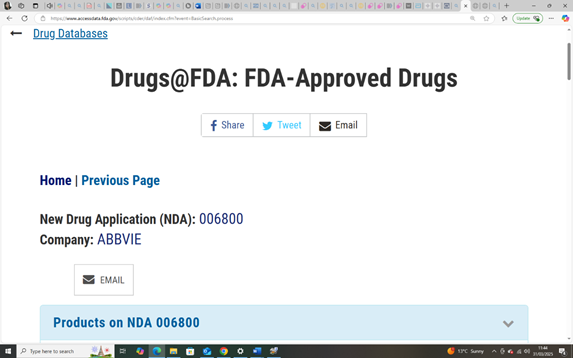

In 1949, the FDA had already approved a different drug: paramethadione, a structural analogue of trimethadione, both part of the oxazolidinedione class of anticonvulsants. Marketed under the name Paradione by Abbott Laboratories, paramethadione was prescribed in the U.S. for absence seizures (NCATS).

Paramethadione (marketed as Paradione by Abbott Laboratories) was distributed in the United States and Canada, where it was prescribed for absence seizures throughout the 1950s and 1960s (CMAJ, 1959; PDR, 1954). To date, aside from Canada, no verified evidence of its approval or distribution has been found in thalidomide-affected regions such as the UK, Australia, or Germany, supporting the theory that paramethadione did not appear in those markets.

Paramethadione: A teratogen quietly removed in Canada after its official last FDA order in 1989, making it impossible to attribute outcome shifts to known regulatory action (FDA, N.D). (See Report Section 12 – Foundational Studies).